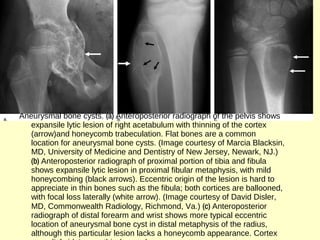

Aneurysmal bone cysts. (a) Anteroposterior radiograph of the pelvis shows

expansile lytic lesion of right acetabulum with thinning of the cortex

(arrow)and honeycomb trabeculation. Flat bones are a common

location for aneurysmal bone cysts. (Image courtesy of Marcia Blacksin,

MD, University of Medicine and Dentistry of New Jersey, Newark, NJ.)

(b) Anteroposterior radiograph of proximal portion of tibia and fibula

shows expansile lytic lesion in proximal fibular metaphysis, with mild

honeycombing (black arrows). Eccentric origin of the lesion is hard to

appreciate in thin bones such as the fibula; both cortices are ballooned,

with focal loss laterally (white arrow). (Image courtesy of David Disler,

MD, Commonwealth Radiology, Richmond, Va.) (c) Anteroposterior

radiograph of distal forearm and wrist shows more typical eccentric

location of aneurysmal bone cyst in distal metaphysis of the radius,

although this particular lesion lacks a honeycomb appearance. Cortex

Aneurysmal bone cysts.(a) Anteroposterior radiograph of the pelvis shows expansile lytic lesion of right acetabulum with thinning of the cortex (arrow)and honeycomb trabeculation. Flat bones are a common location for aneurysmal bone cysts. (Image courtesy of Marcia Blacksin, MD, University of Medicine and Dentistry of New Jersey, Newark, NJ.) (b) Anteroposterior radiograph of proximal portion of tibia and fibula shows expansile lytic lesion in proximal fibular metaphysis, with mild honeycombing (black arrows). Eccentric origin of the lesion is hard to appreciate in thin bones such as the fibula; both cortices are ballooned, with focal loss laterally (white arrow). (Image courtesy of David Disler, MD, Commonwealth Radiology, Richmond, Va.) (c) Anteroposterior radiograph of distal forearm and wrist shows more typical eccentric location of aneurysmal bone cyst in distal metaphysis of the radius, although this particular lesion lacks a honeycomb appearance. Cortex